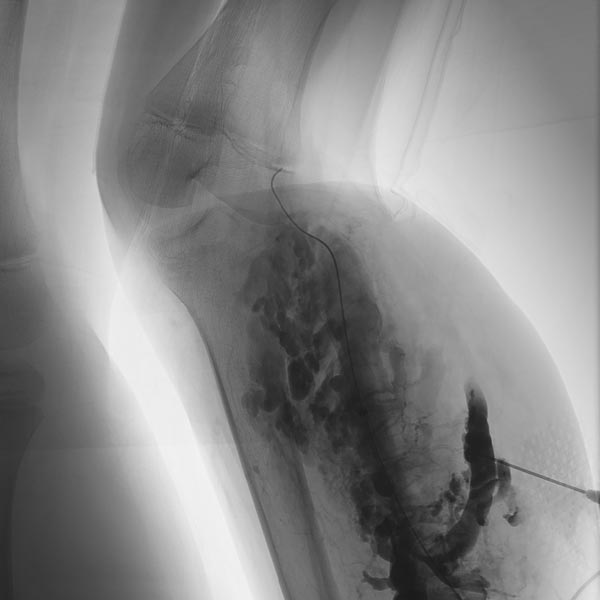

After additional puncture of a very distal part of the large-lumen communicating vein and contrast injection, there is no more outflow into the deep venous system. Thus, even in the long term, the risk of embolism of thrombi from the venous malformation into central conducting veins is eliminated.

Additional sclerotherapy 3 months after the first treatment with polidocanol foam 3% with ultrasound-guided direct puncture. The more proximal parts of the venous malformation are partially occluded, the still open channels of the venous malformation after the first treatment are significantly reduced in size. The former communication with the deep conducting venous system remains occluded. In the meantime, a temporary epiphysiodesis with temporary stapling of the growth plates had been performed for leg length correction on the other side.

A new puncture was performed more proximally on the lower leg because still open parts of the venous malformation were detectable here on ultrasound. After contrast injection, only a few, small-lumen areas of the venous malformation are contrasted. Sclerosing foam can be seen in the cavities of the distal part of the venous malformation (visible as intraluminal radiolucency).